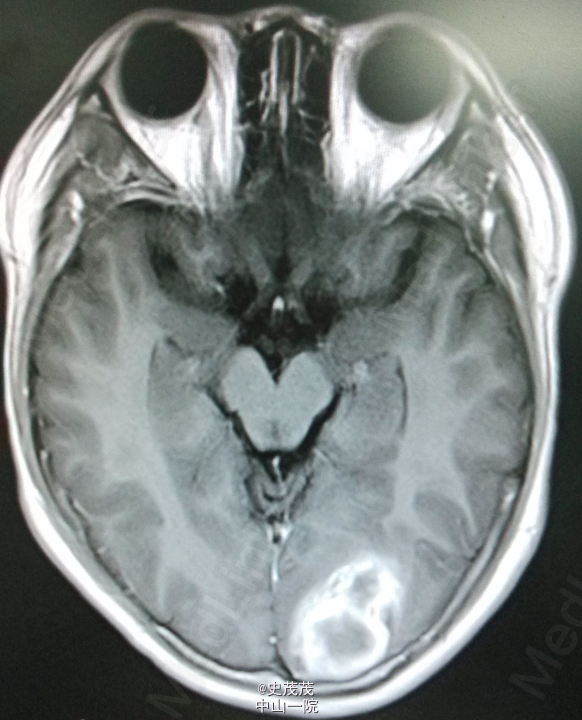

入院查体:神清,对答切题,记忆力及智力粗测正常,双侧瞳孔等大等圆,直径约2.5mm,对光反射灵敏,伸舌居中,耳鼻无异常分泌物,颈软,无抵抗,Kernig Sign(-),粗侧左眼视野变窄,其余颅神经检查未见明显异常,四肢活动好,肌力Ⅴ级,肌张力正常,生理反射存在,病理反射未引出。 辅助检查:CT:左侧枕顶叶片状高密度影伴周围低密度影,病灶范围约2.3cm×3.5cm×34cm,内见钙化灶。颅内动脉VR、MIP重建显示:左侧枕顶叶可见团状异常血管影,部分血管壁可见钙化斑,有左侧大脑中动脉供血。考虑左侧枕顶叶血管畸形并出血,建议复查。头颅DSA提示未看到输出静脉,需鉴别动静脉畸形及肿瘤。 头部MR增强扫描+头部血管扫描:左侧枕顶叶团块状异常信号影,大小约3.6×2.4×3.4cm,T1WI呈高低混杂信号,T2WI呈高信号,周围可见大片水肿区,增强后病变边缘有小片状强化影,肿块内见粗大血管影,肿块血管与邻近大脑中动脉、大脑中浅静脉关系密切。诊断提示左侧枕顶叶病变,考虑肿瘤与血管畸形鉴别,前者可能性大,合并出血,建议进一步检查